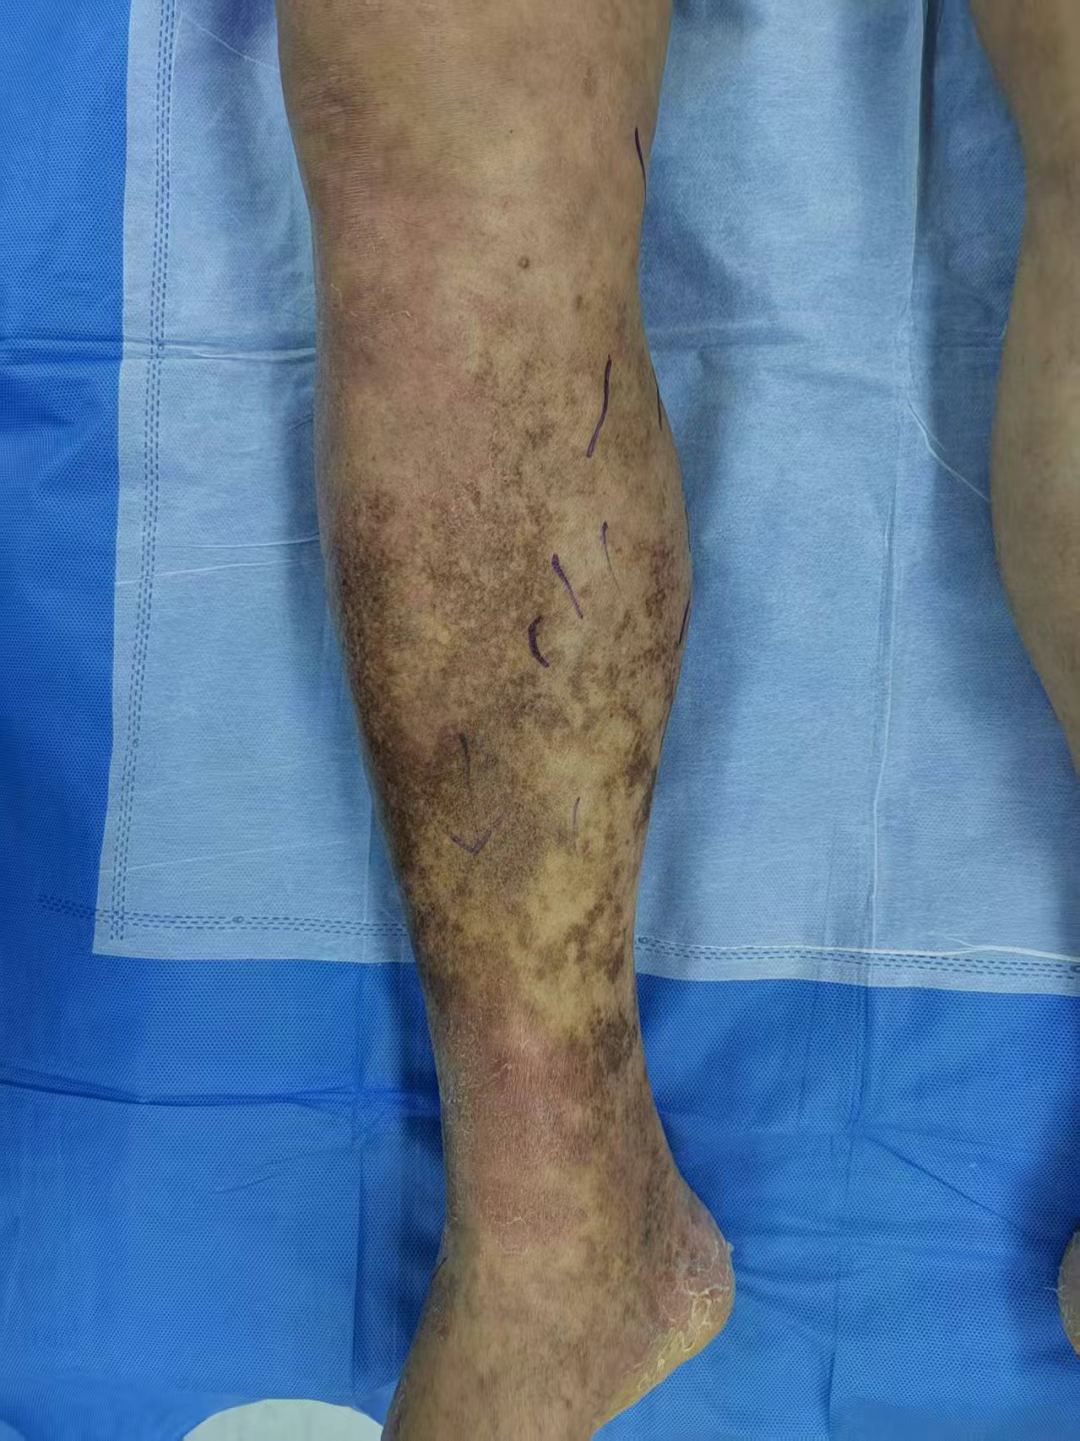

一、皮肤色素沉着:

从微红到褐黑,静脉在 “染色”

很多静脉曲张患者会发现,小腿内侧或脚踝处的皮肤慢慢变了颜色:起初是淡淡的微红,后来逐渐变成褐色、深褐色,甚至像被 “污渍” 染过一样。这其实是血液淤积的 “后遗症”。当静脉瓣膜失效,血液长期淤积在下肢静脉中,静脉压力会持续升高。这会导致红细胞 “挤破” 血管壁,跑到周围组织里。红细胞破裂后释放出的含铁血黄素,是一种棕褐色的物质,长期沉积就会让皮肤变色。这种色素沉着一旦出现,就很难完全消退,而且往往意味着静脉曲张已经发展到一定程度,皮肤的营养供应开始出现问题。

五、老烂腿:

从溃疡到难愈,静脉曲张的 “终末伤害”

“老烂腿” 是老百姓对下肢慢性溃疡的俗称,也是静脉曲张最严重的并发症之一。当静脉压力长期居高不下,皮肤营养严重缺乏,再加上轻微的外伤(比如碰破、蚊虫叮咬),就可能出现皮肤破溃,而且一旦破溃就很难愈合。

这种溃疡多发生在脚踝内侧,初期可能只是一个小伤口,但会逐渐扩大、加深,流出渗液,甚至散发异味。患者往往疼得难以走路,而且溃疡反复不愈,可能持续数年,严重影响生活质量。